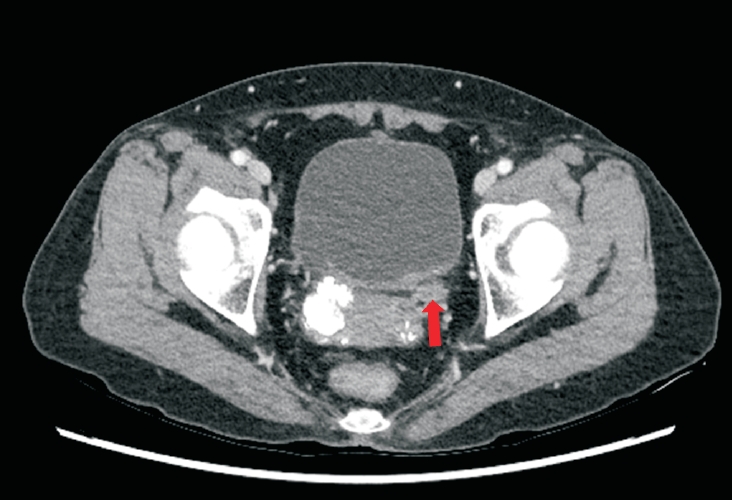

During the post–TUR-BT period, her lower urinary tract symptoms were managed medically with an α-blocker (silodosin), an anticholinergic agent (fesoterodine), and Uro-vaxom. She had been maintained on a surveillance protocol consisting of periodic cystoscopy and abdominopelvic computed tomography (CT). A follow-up CT scan performed in November 2024 identified a new mass lesion in the left distal ureter accompanied by hydronephrosis (Fig. 1). This finding prompted concern about possible malignant disease and led to the decision for surgical exploration in March 2025 (Table 1).

Fig. 1.

Contrast-enhanced computed tomography showing focal wall thickening of the left lower ureter (red arrow).

Fig. 1. Contrast-enhanced computed tomography showing focal wall thickening of the left lower ureter (red arrow).